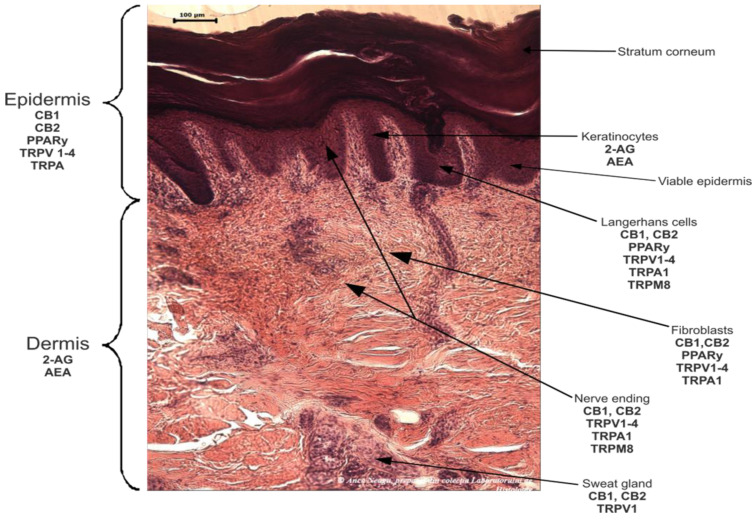

The human endocannabinoid system consists of the two cannabinoid receptors CB1 and CB2; several endogenous ligands such as 2-arachidonoylglycerol (2-AG) and N-arachidonoylethanolamine (anandamide) (AEA); and enzymes involved in the synthesis, transport, and degradation of endocannabinoids [ref. 2]. Both CB1 and CB2 skin receptors, which are present in epidermal keratinocytes, cutaneous nerve fibers, dermal cells, melanocytes, eccrine sweat glands, and hair follicles [ref. 96,ref. 97,ref. 98], can be modulated by endocannabinoids, with the most studied being N-arachidonoyl ethanolamide (AEA), 2-arachidonoyl glycerol (2-AG), N-palmitoyl ethanolamide (PEA), N-alpha-linolenoyl ethanolamide (ALEA), N-linoleoyl ethanolamide (LEA), N-oleoyl ethanolamide (OEA), N-stearoyl ethanolamide (SEA), N-eicosapentaenoyl ethanolamide (EPEA), and N-docosahexaenoyl ethanolamide (DHEA) [ref. 99,ref. 100,ref. 101,ref. 102,ref. 103]. However, endocannabinoids also bind to other receptors found in various skin cells, such as transient receptor potential (TRP) channels, which are involved in a variety of processes, including the development and preservation of the skin barrier, cell growth stimulation, and cell differentiation. They also play a significant role in immunological and inflammatory processes [ref. 72]. Endocannabinoids interact with PPARs via direct or indirect signaling pathways. Biological processes like neuroprotection, anti-inflammation, and analgesic action are partially mediated by PPAR activation [ref. 59]. ECS’s involvement and role in cutaneous biology is currently an intensely debated research topic both in clinical and preclinical studies [ref. 104,ref. 105]. Topical applications of cannabinoids provide therapeutic benefits for the patient in multiple pathologies like psoriasis, eczema, and atopic dermatitis, as shown in Figure 1 [ref. 59]. These advantages are obtained due to the remarkable role of the ECS in improving dermatological conditions symptoms such as itching, inflammation, and pain.

The skin, which is the largest organ in the human body and serves as a barrier between the body and the outside world as well as an immunological function, is made up of three layers, the dermis, the epidermis, and the stratum corneum (SC) [ref. 145,ref. 146,ref. 147,ref. 148], as shown in Figure 2 and Figure 3.

The skin has unique characteristics: It is permeable relative to the environment and allows the diffusion of air, heat, water, and low molecular weight molecules [ref. 145]. Skin permeability can occur in three different ways: the intercellular pathway, which involves the space between corneocytes and keratinocytes; the transcellular pathway, which involves corneocytes and the lipid matrix around them; and the appendicular pathway, which involves sweat glands and hair follicles [ref. 149]. Because of this, transdermal application can be used as an alternative method of drug administration. This is because it is simple to use and because it is administered directly into the systemic circulation, avoiding the first hepatic passage and the potential appearance of unwanted metabolites; moreover, the necessary dose and side effects can be significantly reduced [ref. 73,ref. 150,ref. 151].